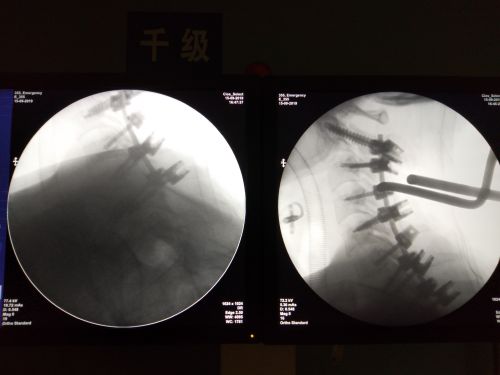

沈雄杰教授等为患者施行急诊手术。

术后椎体序列排列整齐,颈椎稳定性良好。

完善相关检查、分析讨论病情并制订手术方案后,沈雄杰教授带领团队为患者施行急诊全麻下颈椎后路减压复位植骨内固定术。手术前后历时6个小时,成功对骨折的颈椎与胸椎部位进行螺钉固定,缓解了碎骨片对脊髓的压迫。